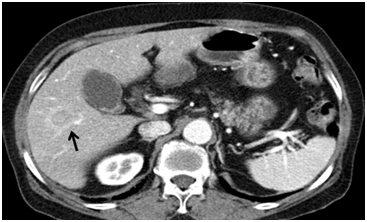

A 72-year-old woman was incidentally found to have a 2.2cm solitary tumor in the right inferior segments on computed tomography (CT). The patient had undergone endoscopic retrograde cholangiopancreraticography (ERCP) one year prior for treatment of cholangitis due to common bile ducts stones. Several gallbladder stones were identified. Cholecystectomy was recommended at that time, but the patient deferred surgery. A liver mass was subsequently identified on follow-up CT, in addition to several gallstones. The patient was asymptomatic. She had no history of alcohol abuse or hepatitis B or hepatitis C viral infection. Blood cell counts and liver enzymes were unremarkable. Alpha fetoprotein (AFP), carbohydrate antigen 19-9 (CA19-9) and carcinoembryonic antigen (CEA) were also within their normal reference ranges. On contrast-enhanced CT scan (non-dynamic CT), the lesion in the S5/6 segment demonstrated heterogeneous enhancement and was described as cholangiocellular carcinoma (Figure 1). Liver magnetic resonance image (MRI) revealed a T1 hypointensity and T2 hyperintensity round well-defined mass. This mass was slightly enhanced in the arterial phase and subsequently washed-out in the portal phase (Figure 2). Hepatocellular carcinoma was highly suspected based on these MRI findings.

Figure 1 Contrast-enhanced CT scan. The lesion in segment S5/6 demonstrates heterogenous enhancement and is described as cholangiocellular carcinoma.